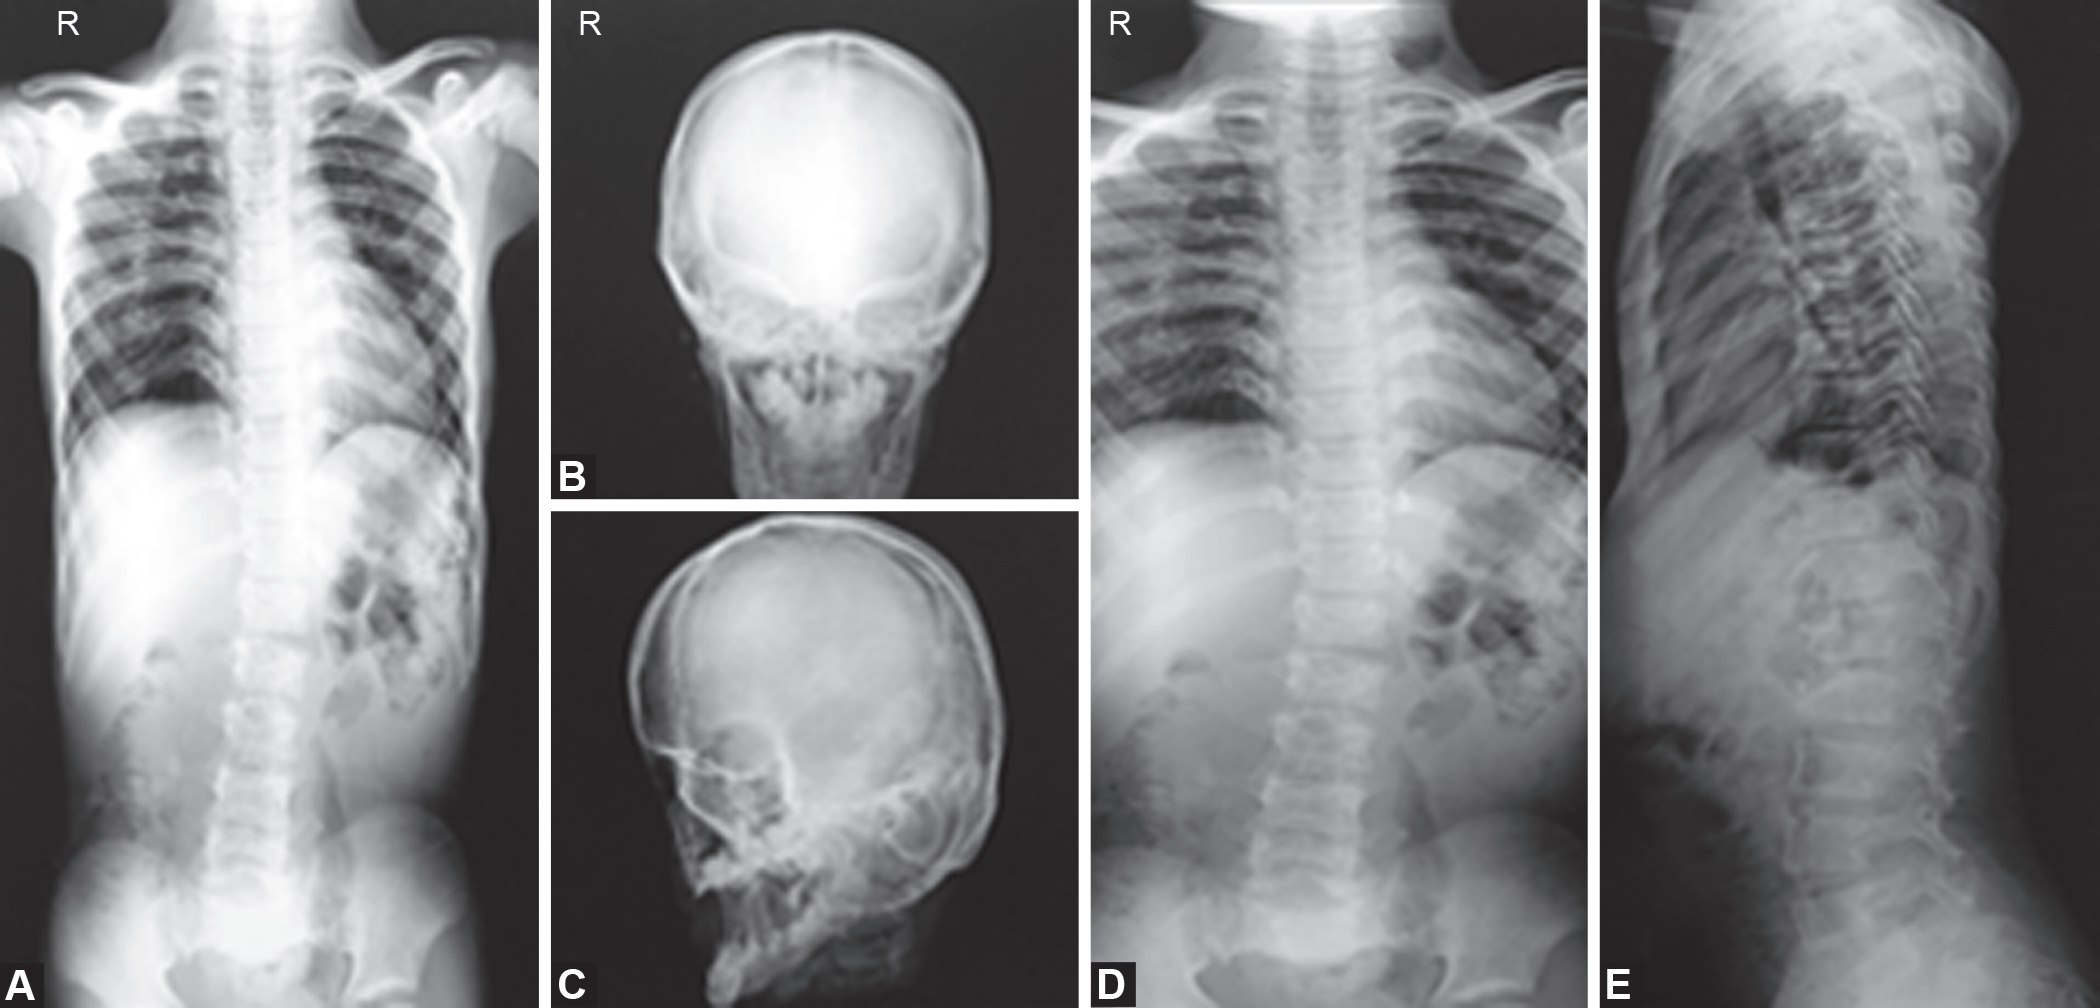

影像学照片

脆骨病的诊断及特点

影像学和分子诊断技术的进步,可以实现在妊娠早期诊断。而轻度的成骨不全症有时直到成年才能被发现以前,大多数病例只能在妊娠中期使用超声(US)检查,若怀疑为成骨不全症,明确诊断需要侵入性基因检测。

脊椎侧凸是OI患者常见的并发症,部分严重者可影响呼吸功能甚至危及生命。外固定矫形支架能缓解疼痛及腰椎后凸,并加强活动能力,但可导致胸廓变形,且对防止侧凸进展效果不大,并可能进一步加重肺功能。

脊柱侧凸Cobb角>30、且年龄为11~12岁的0I患者,需要临床随访及定期x线检查,如果侧凸进展明显,则应及时进行矫形手术,并且术后应保持脊柱稳定。成人OI患者常发生听力缺失,起初仅是传导性听力缺失,随着疾病进展,感觉性听力缺失也逐渐出现,因此建议青春期后每3~5年需对0I患者的听力进行监测。针对听力缺失的治疗,疾病开始仅需应用助听器即可达到治疗效果,随着听力缺失进一步加重,患者需行镫骨切除术,其治疗效果较好。